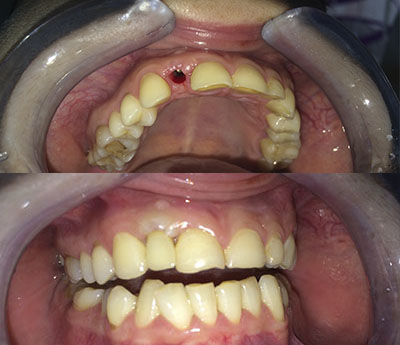

Il sistema Fast&Fixed è un'alternativa immediata. Questa procedura ti permetterà di ritrovare il tuo sorriso in un unico intervento. Il risultato è immediato e recupererai autostima e fiducia in te stesso.